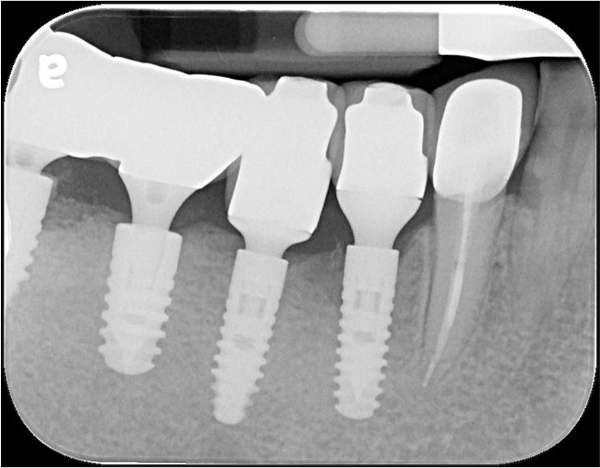

術後X光

治療後X光,穩合度良好